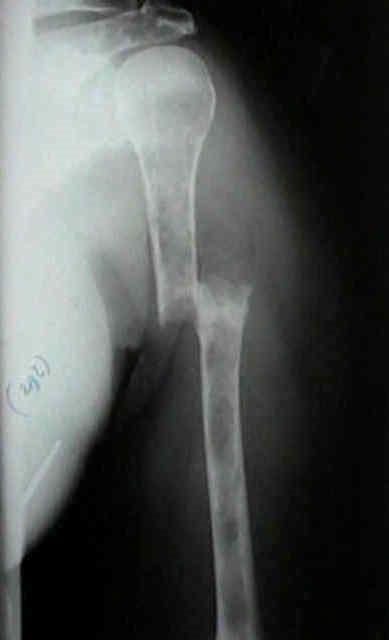

Myeloma Bone Disease

Myeloma in hand

Myeloma in the orbit

MRI (with contrast or STR images) very useful to delineate problems